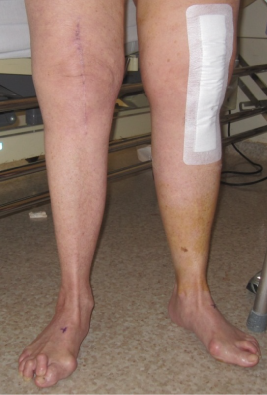

Post operatively, full ROM and full weight bearing was permitted from post-operative day two. By six week follow up the patient was fully weight bearing without any aids; radiographs demonstrated bony union at the osteotomy site with good alignment (Figure 4–6). At one year review, the patient was pain free, with a ROM of 0° to 110° without a quadriceps lag, and with clinically acceptable alignment (Figure 7). Pre and postoperative knee scores are listed in Table 1.

Figure 4 Preoperative alignment view of the leg.